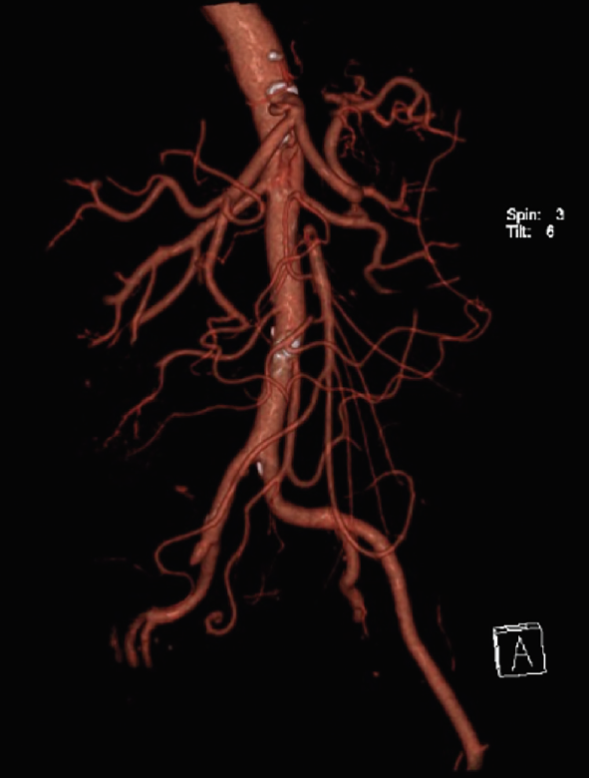

A su ingreso se solicitaron laboratorios generales, los cuales mostraron leucocitosis y anemia normocítica normocrómica grado I de la OMS, el resto de los estudios de laboratorio fueron reportados dentro de los parámetros establecidos por laboratorio; se decidió ingreso hospitalario para abordaje diagnóstico por anemia y gastropatía; se solicitaron estudios de laboratorio de extensión, los cuales reportaron sangre oculta en heces cualitativa positiva y examen general de orina con bacterias escasas. Se inició tratamiento con ceftriaxona y pantoprazol. Al persistir con intenso dolor abdominal, se solicitó tomografía abdominal simple, la cual sugirió trombosis mesentérica, por lo que se realizó complemento con angiotomografía abdominal, que reportó los siguientes resultados: trombosis segmentaria (figura 1) y en la totalidad de la luz de la arteria mesentérica superior con longitud de 37 mm, y posterior recanalización por vascularidad colateral (figura 2), trombosis de la iliaca externa derecha a 9 mm de su nacimiento, que se extiende hasta arteria femoral con opacificación distal (figura 3).

Figura 3 Reconstrucción volumétrica de angiotomografía en fase arterial que demuestra defecto de llenado en el nacimiento de la arteria mesentérica con recanalización, así como trombosis de la arteria iliaca externa derecha que se extiende la arteria femoral ipsilateral.